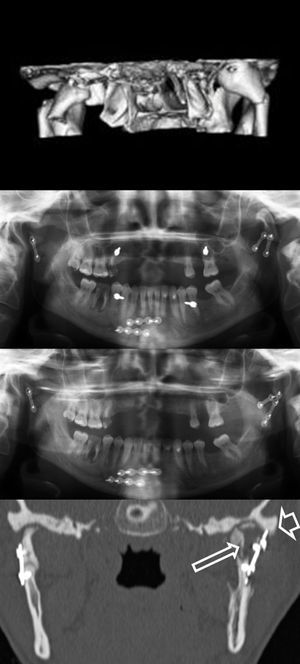

Figura 5.Fractura bicondílea y parasinfisaria. Se observa en la imagen 3D la luxación completa a medial del cuello y la cabeza del cóndilo izquierdo. Tras la primera cirugía, la OPG de control mostró la cabeza del cóndilo fuera de la fosa glenoidea. En la segunda cirugía se consiguió una adecuada reducción y alineamiento, objetivada en una nueva OPG. La TC (corte coronal) demuestra la afectación de la medular de la cabeza del cóndilo (flecha larga), a consecuencia de una infección posquirúrgica y el material de osteosíntesis impactado en el borde externo de la fosa glenoidea (flecha corta). En el momento de la redacción de este manuscrito, la paciente estaba pendiente de la retirada de la placa.